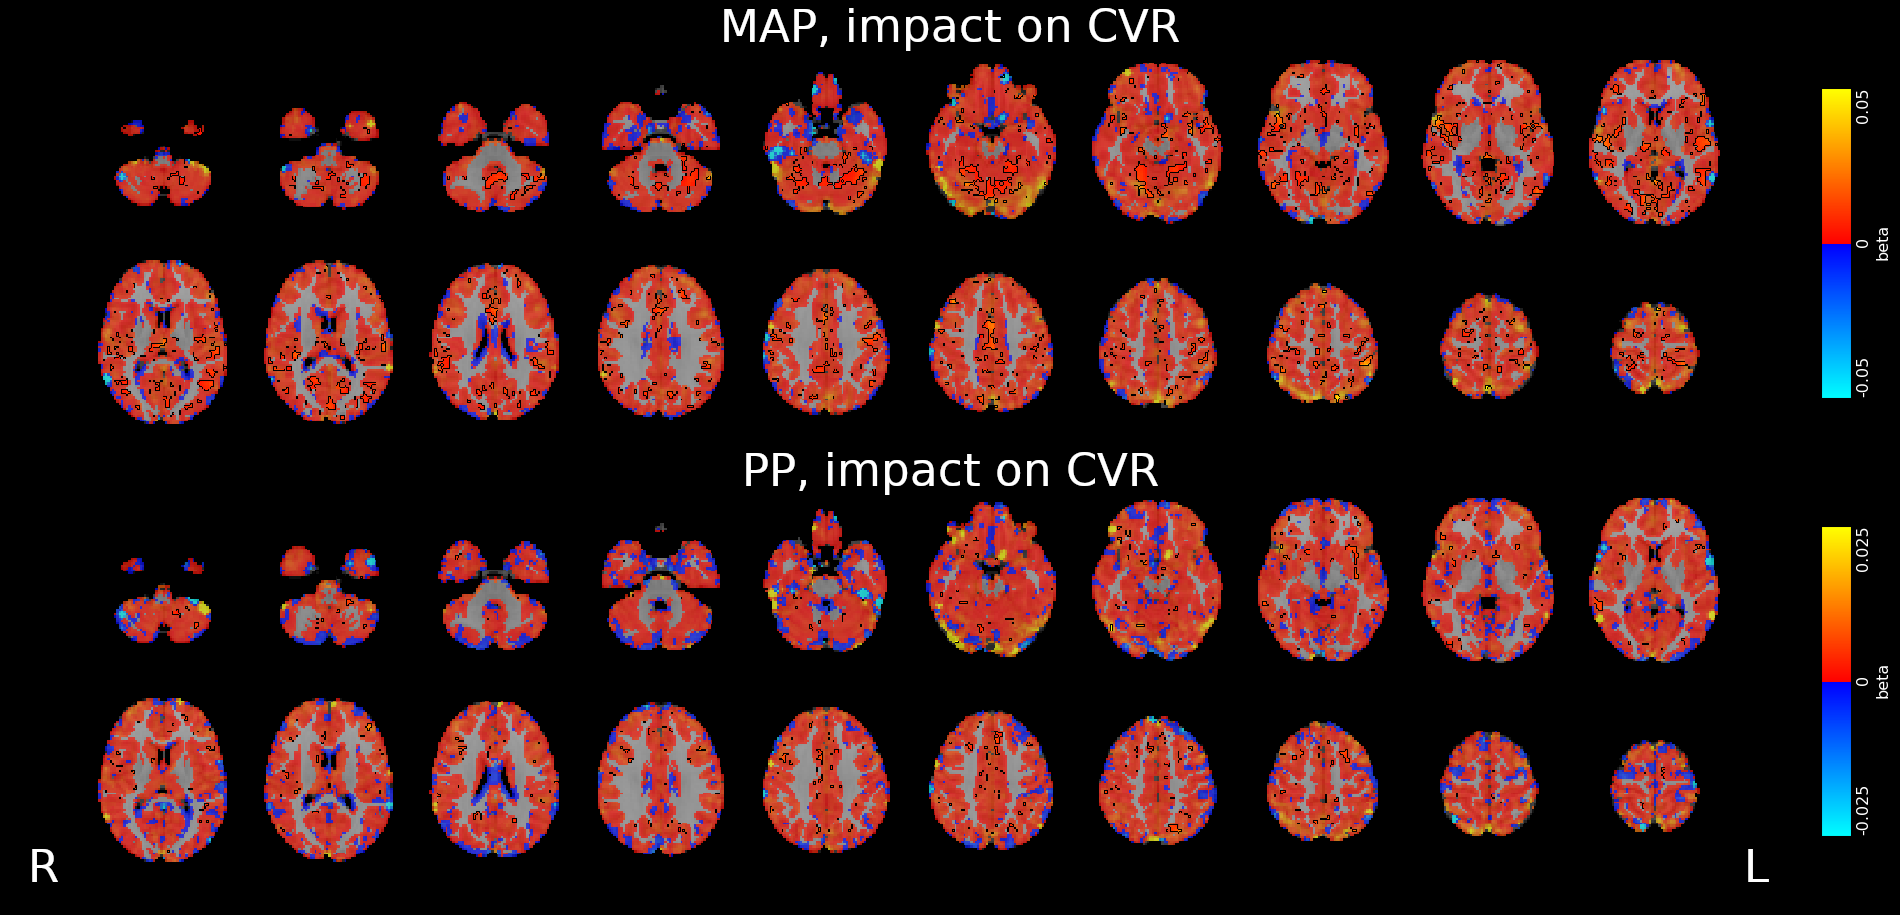

CVR and blood pressure

Due to its nature as homeostatic and cerebrovascular process, CVR is modulated by systemic changes in blood pressure¹

1. Fierstra et al. 2013 (J. Physiol.); 2. e.g. Hetzel et al. 1999 (Stroke)

Previous studies with Transcranial Doppler Ultrasound suggest to take into account blood pressure when measuring CVR²

To our knowledge, the impact of blood pressure on BOLD-fMRI based CVR estimation has not been assessed yet

We averaged the two measurements and computed the Mean Arterial Pressure (MAP) and the Pulse Pressure (PP):

Methods: effect of pressure

We used 3dLMEr¹ to set up the following LME models:

Results were thresholded at \(p<0.05\) after controlling for false discovery rate²

1. Chen et al. 2013 (Neuroimage); 2. Benjamini et al. 2006 (Biometrika)

*maps were smoothed 5mm FWHM

Methods: effect of pressure

We smooth CVR and lag maps using a dilated GM mask (white mask below) and a FWHM of 5mm (voxel size 2.5 isometric) before running 3dLMEr.

Results: blood pressure

Results: blood pressure

Results: blood pressure

Both MAP and PP should be taken into account in CVR experiments, especially in comparisons between subjects or between regions!

- Stationary blood pressure changes, expressed as MAP and PP, as well as sex, impact regional CVR estimation differently across sessions and subjects

-

Dynamic blood pressure changes are expected to impact CVR estimation, hence continuous blood pressure recordings are required to assess the matter